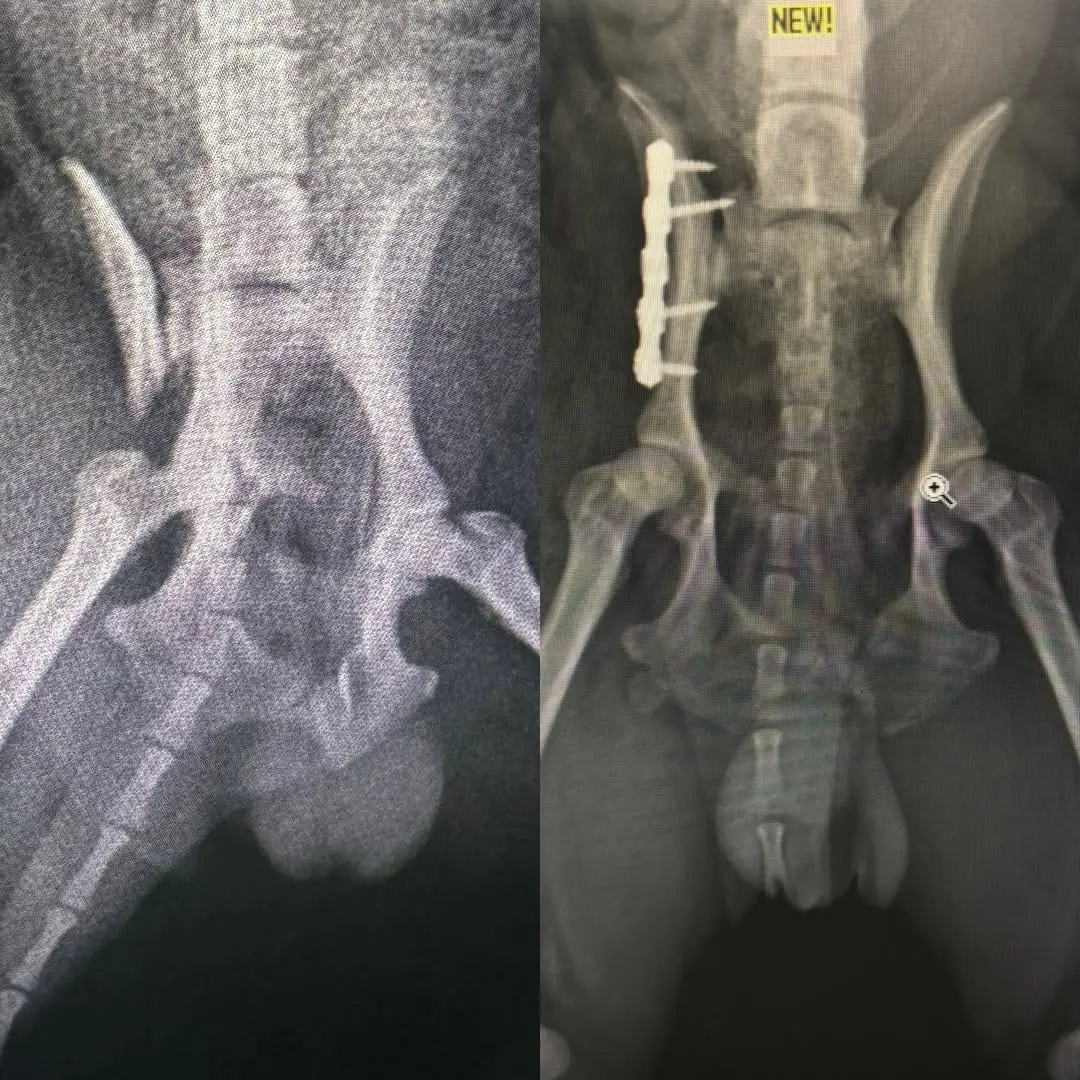

Kırık Ameliyatları: Kemik kırıkları, plak, vida ve tel sistemleri kullanılarak onarılır.

Pelvis ve Kalça Kırıkları: Parçalı pelvis kırıkları ve kalça çıkıkları, özel tekniklerle tedavi edilir.

Görüntüleme ve Tanı: Röntgen, ultrason gibi görüntüleme yöntemleriyle tanı konulur.

Tedavi Planı: Elde edilen bulgulara göre, en uygun tedavi planı oluşturulur.

Cerrahi Müdahale: Gerekli görülürse, cerrahi müdahale gerçekleştirilir.